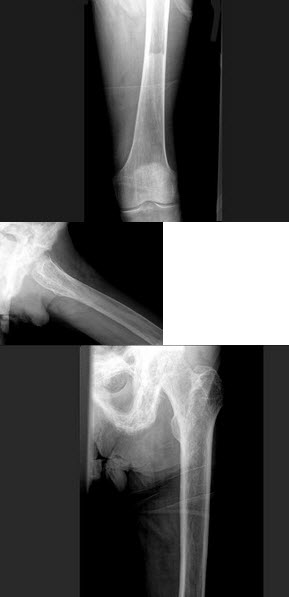

70、单项选择题

女,1岁,身体发育异常,眼巩膜呈蓝色,结合图像,最可能的诊断为()

A.成骨不全

B.粘多糖病

C.软骨发育不全

D.佝偻病

E.侏儒症